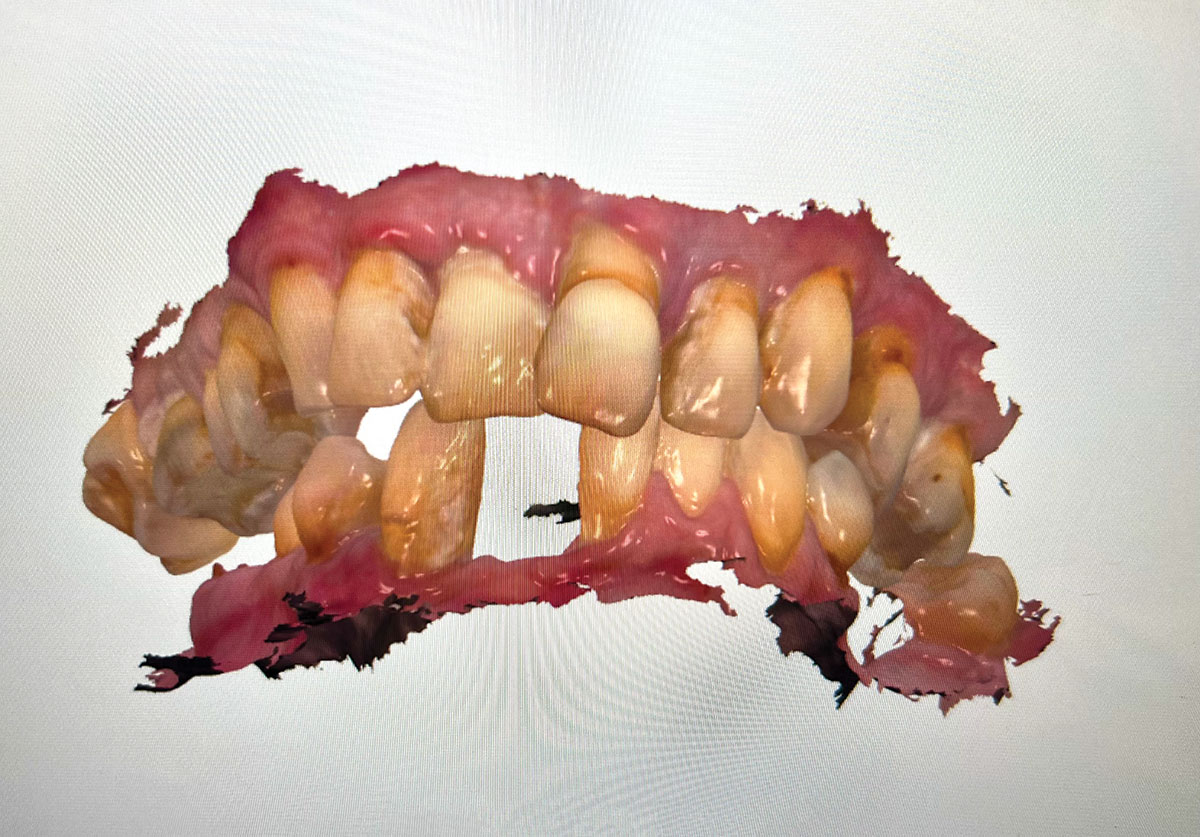

Fig 2. Initial presentation, intraoral view.

Figure 2

Fig 10. Initial clinical situation, intraoral view.

Figure 10